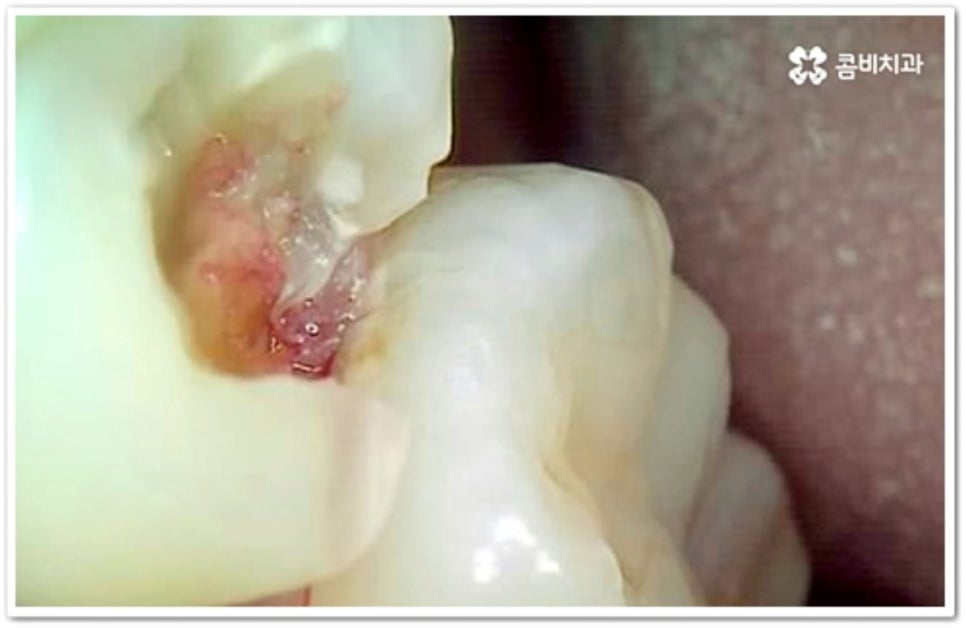

치아의 구조를 살펴보면 안쪽의 무른 조직을 감싸고 있는 단단한 바깥쪽 법랑질은 교합면에서 가장 두껍고 잇몸쪽으로 갈수록 얇아지기 때문에 인접면에 생긴 충치의 경우 조금만 진행 되어도 손상이 내부 신경까지 보다 빠르게 번질 수 있어요. 신경치료를 받은 치아는 정상 치아에 비해 외부 충격에 취약해지므로 가능한 한 그 단계에 이르기 전에 적절한 치료를 받으실 필요가 있는데요.

인접면에 충치가 생겼을 때 치료 과정은 손상 정도에 따라 달라질 수 있는데 만약 아주 경미하다면 바로 레진으로 이를 수복할 수 있겠지만 치아 경계면이 무너졌다면 직접적인 레진 수복으로는 생리학적 형태를 재현하기 까다롭기 때문에 본을 떠서 외부에서 금이나 세라믹 보철물을 만들어 끼워넣는 간접적인 방법을 통해 도움을 받을 수 있어요. 환자분들의 상황에 따라 치아 일부만 수복해야 할 때는 인레이 치료를 하고 손상이 크면 신경치료를 한 후 필요시 내부에 기둥을 세우고 치아 전체를 다듬어 씌우는 크라운 치료를 이용하게 될 거예요.